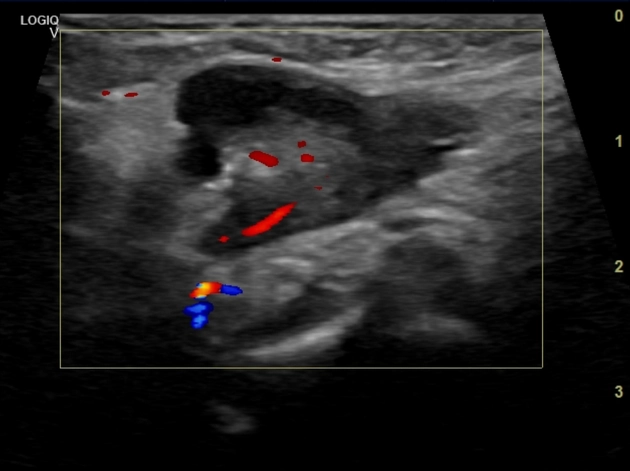

Thoát vị ống Nuck (Canal of Nuck hernia)

Nang nước ống Nuck (Hydrocele of the canal of Nuck)